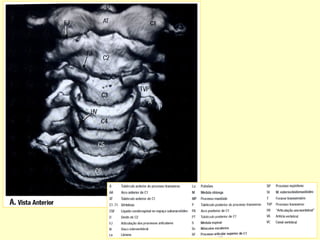

ESTRUTURAS DAS VÉRTEBRAS

1 – Um arco vertebral

2 – Um corpo vertebral

3 – Um processo espinhoso

4 – Dois processos transversos

5 – Quatro processos articulares

B - Vista Superior